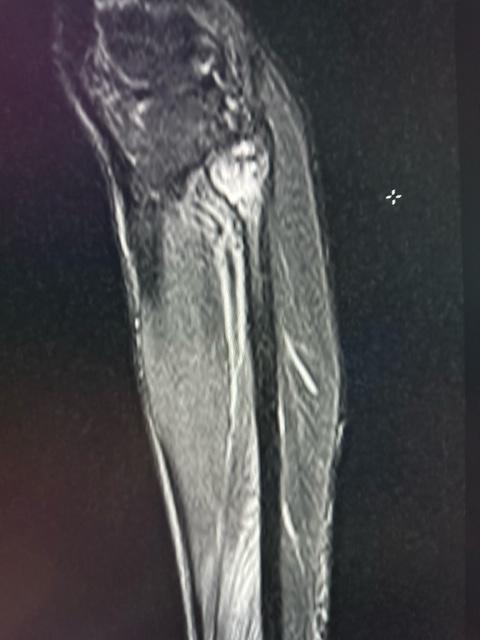

ACL and Anterior Horn Lateral Meniscus

Great comments. Begin forwarded message: if ant horn is torn with acl inj i see three patterns- mc incomplete radial at junction of ant horn and body 2nd common- vertical tear like this 3rd common as part of bucket handle tear- mc anteriorly displaced double delta- have seen two cases of posterior double delta also. […]